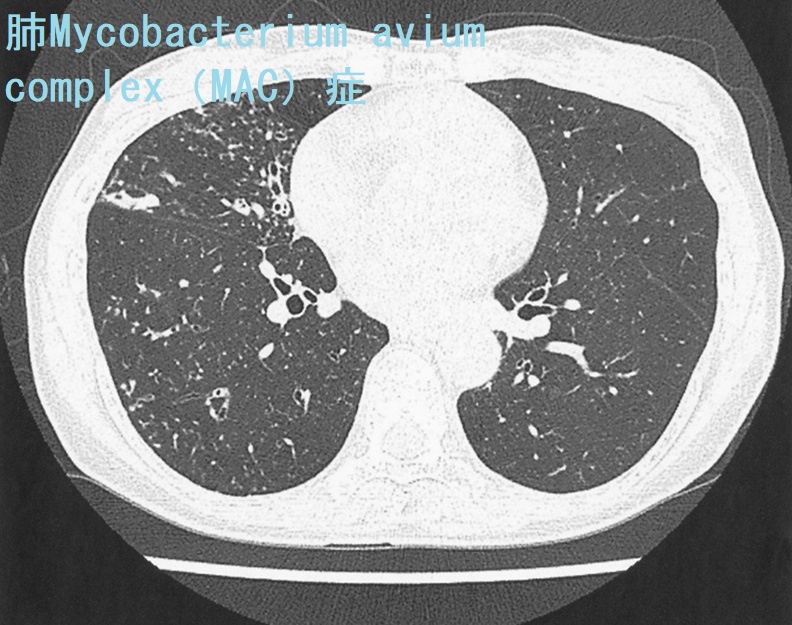

- 結核と似ているけど違う非定型抗酸菌症(非結核性抗酸菌症)

「結核菌」「ライ菌」以外の抗酸菌は「非定型抗酸菌(非結核性抗酸菌)」です。自然界に広く存在し、甲状腺機能低下症や糖尿病他免疫不全者に感染します[Infect Chemother. 2017 Nov 8;50(1):59–64.]が、人から人への感染はなく、隔離の必要はありません。

非定型抗酸菌症(非結核性抗酸菌症)は増加傾向です。肺Mycobacterium avium complex(MAC)症は、特に患者数が急増しており、結核死亡者数を超えているともされます。

非定型抗酸菌症は男性35%、女性65%、いずれも70歳代の高齢者に多い。

Mycobacterium avium complex(MAC)が約9割で最も多く、Mycobacterium kansasii、Mycobacterium abscessusがみられる。Mycobacterium kansasii、MAC、Mycobacterium intracellulareは遅速発育菌ですが、最近は難治性の迅速発育菌(M.abscessus)が増加傾向です。

遅速発育菌は寛解増悪の自然経過をとり、微熱、断続的な血痰などを繰り返します。

肺CTの線維空洞・小結節/浸潤性(円筒状)気管支拡張陰影(signet rng sign, tram line, tree in bud pattern)は非定型抗酸菌を疑う所見ですが、実際、細菌性の方が多い。空洞があると予後は悪くなります。

肺非結核性抗酸菌症の診断は、

- 喀痰抗酸菌培養検査(菌種同定を行うことにより、確定診断が得られる。自然界のものが混じるため、必ず2回以上行う)

- M.avium、M.intracellulare PCRも併用

- 痰が出ない場合や診断が難しい場合、気管支肺胞洗浄液で培養されれば確実性が高い

最近開発されたキャピリアMAC抗体(抗酸菌抗体定性)は感度70%・特異度90%(アビウム、イントラセルラーレ合わせてMAC:全体の70%)で有用。MAC抗体(抗酸菌抗体定性)は過去の非定型抗酸菌(非結核性抗酸菌)曝露によっても陽性になるので、現在の活動性を反映しません。

肺非結核性抗酸菌症は診断確定しても、必ずしも全員に治療を行う訳ではありません。空洞、塗抹陽性、血痰・喀血などがあれば積極的に治療を考慮する。

高齢者や結節性気管支拡張だけでは、経過観察になる事が多い。

多くの抗菌薬に自然耐性があるため、薬が効きにくい。治療はクラリスロマイシン+抗結核薬2 剤(リファンピシン・エタンブトール)の3 剤併用療法が基本ですが、多くは治療抵抗性。リファンピシンは薬剤性甲状腺機能低下症の原因です。

非定型抗酸菌の1.8%に肺癌を合併するとされ、注意を要します。

72歳のインスリン依存性糖尿病+甲状腺機能低下症/橋本病患者におきたMycobacterium avium intracellulareを起因菌とする急性化膿性甲状腺炎の報告があります[J Endocrinol Invest. 1994 Feb;17(2):133-4.]